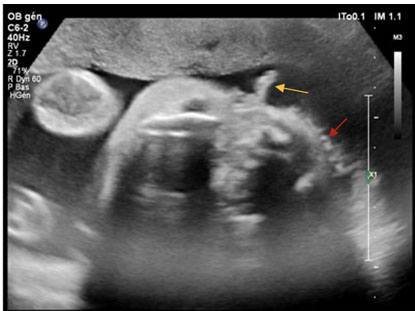

A 63-year-old male presented to the emergency department following a two-week history of a swollen and tender right cheek. The patient had a history of diabetes, with the most recent test performed six weeks prior to the infection showing an A1C of 10.5. The patient also had a history of cirrhosis, and HIV, for which he was being treated with Cabenuva. The patient reported having multiple cosmetic procedures performed in the past, including zygomatic implants, injectable facial fillers, with his last cosmetic procedure being implant replacements following an infection of an unknown organism in 2012. Upon examination, infection was suspected, and the patient was sent for a CT scan as well as a needle aspiration of the right cheek for analysis. The CT scan indicated the presence of a peripherally enhancing organized fluid collection overlying the right zygomatic bone, surrounding the right zygomatic implant measuring about 5 × 1.3 cm axially and 2.3 cm craniocaudally (Figure 1). The fluid collection was surrounded by mild fat stranding as well as mild asymmetric thickening of the overlying skin. The CT scan also showed multiple other hypodense structures located on the left side over the left zygomatic bone (Figure 2), along the inferior margin of the left zygomatic facial implant and lateral to the left maxilla (Figure 3), all favored to represent cosmetic facial fillers. The abscess was surgically drained three days later, and the implant as well as the surrounding fillers were removed. Only the implants and fillers on the affected side were removed as the physician was concerned about the possible risk of spreading the infection. The patient was seen one week later, and no signs of any residual infection were seen, but the patient was still experiencing swelling and discomfort. At this time, the patient was informed that the results from the needle aspiration came back positive for Candida albicans, for which the patient was treated with a two-week course of fluconazole. The patient was seen again in clinic three weeks later and showed no signs of swelling or discomfort following the completion of the 2-week course of fluconazole.

Figure 2: Axial plane CT face with contrast. The infectious collection in the soft tissues of the right hemi-face extends superiorly to the right temple (dotted arrow). On the left temple, a subcutaneous well defined hypodense structure is seen, consistent with a facial filler (solid arrow).